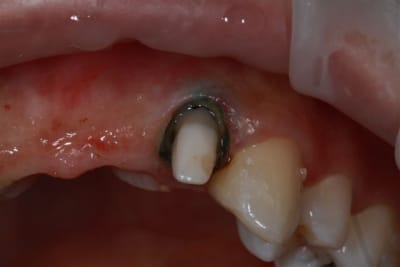

Donc dans un premier temps,je décide d'essayer de retraiter 12/22, de toute façons ça ne peut pas être pire que ce qui tiens depuis 10 ans... enfin 12 mobilité quasiment 3.

ensuite Srew post (bouh...) et résine, afin de pouvoir poser un provisoire et réfléchir à l'avenir du parodonte...car il va y avoir un problème quelle que soit la solution choisie.